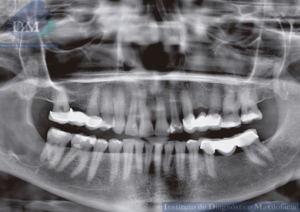

Paciente femenina de 32 años de edad acude al instituto de Diagnóstico maxilofacial – IDM (surco) para evaluación imagenológica de terceros molares. En la radiografía panorámica